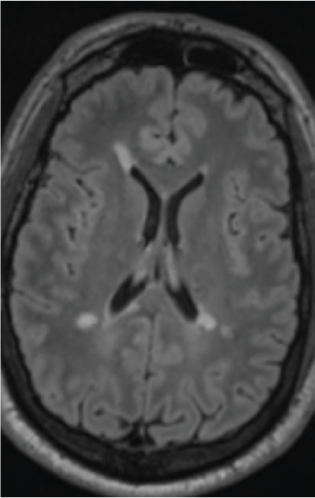

A complete neurologic history was obtained, confirming multiple previous demyelinating events. Neurologic examination was notable for residual right internuclear ophthalmoplegia and central scotoma, without weakness, sensory deficits, or ataxia. Brain magnetic resonance imaging (MRI) before fingolimod discontinuation demonstrated multiple ovoid, periventricular, and cortical/juxtacortical lesions, including at least one new lesion (Figure 2 and Figure S1, which is published in the online version of this article at ijmsc.org).

Brain magnetic resonance image at diagnosis of pulmonary cryptococcosis